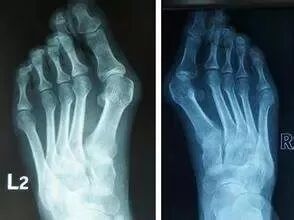

拇外翻,俗稱大腳骨,是引起足部不適的常見(jiàn)疾病之一。18~65歲成年人中發(fā)病率約為23%,成年女性發(fā)病率高達(dá)30%。

拇外翻:腳趾都被“穿歪了”

根據(jù)具體病情進(jìn)展,拇外翻分為4個(gè)階段: